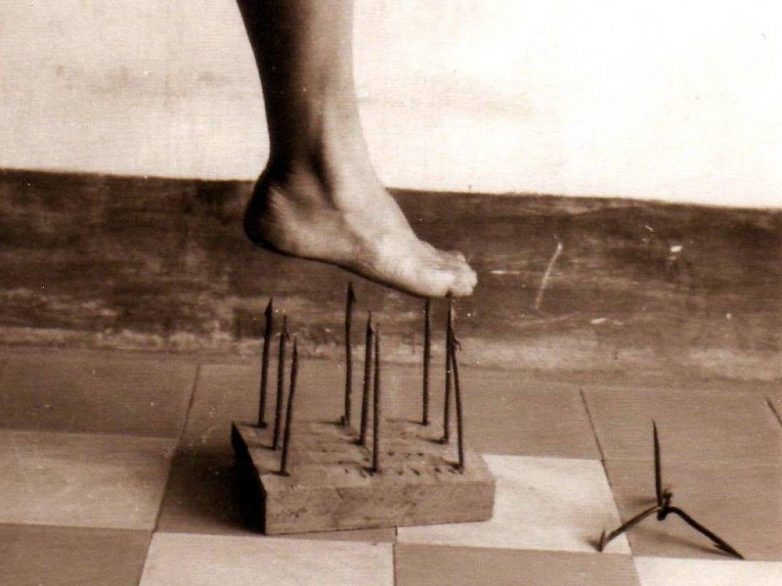

Врожденная нечувствительность к боли

Люди, у которых есть синдром врожденной нечувствительности к боли, абсолютно не чувствуют боль. Многие подумают, что это подарок судьбы, но необходимо знать о том, что организм реагирует болью на заболевание. Мозг посылает сигналы к определенным местам в организме, чтобы человек оградил себя от причины боли, например отдернул руку, чтобы не получить ожог. Если у человека синдром нечувствительности к боли, то последствия могут быть даже смертельными. Такие люди должны осматривать себя несколько раз в день, чтобы убедиться в том, что их здоровью ничего не угрожает: переломы, кровотечения и т.д.

Люди, у которых есть синдром врожденной нечувствительности к боли, абсолютно не чувствуют боль. Многие подумают, что это подарок судьбы, но необходимо знать о том, что организм реагирует болью на заболевание. Мозг посылает сигналы к определенным местам в организме, чтобы человек оградил себя от причины боли, например отдернул руку, чтобы не получить ожог. Если у человека синдром нечувствительности к боли, то последствия могут быть даже смертельными. Такие люди должны осматривать себя несколько раз в день, чтобы убедиться в том, что их здоровью ничего не угрожает: переломы, кровотечения и т.д.Аллергия на воду